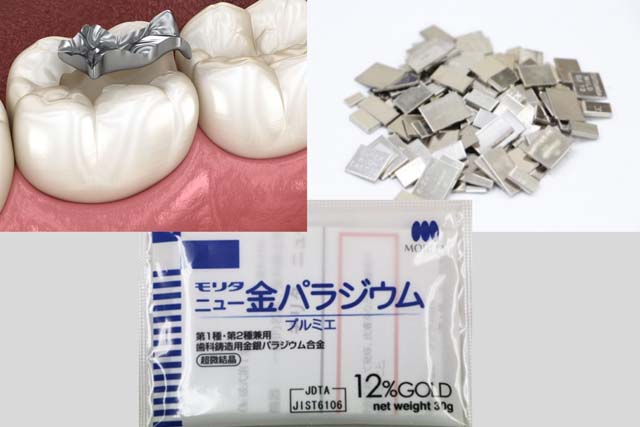

歯の保険治療に今も使われる「アマルガム」や「金銀パラジウム合金」、「ニッケルクロム合金」という金属材料には、身体に悪い影響を与えると言われる水銀や重金属が含まれています。

これらの金属材料は、戦後間もない物資の乏しい時代に、貧しい日本でも国が保険治療用に提供できる金属だったため、保険用として指定されました。

つまり、これらの材料が国の基準をクリアしていたのは、日本が貧しかったころにできた制度なのです。

戦後まもなく国が貧しかった当時の状況で、安全性と金属の原価をはかりにかけて採択された素材、それが今もなお使われている保険で認められている歯科の金属です。

今、治療後に多くの患者さまのお口の中に入っている「銀歯」の金属が、溶け出して体の中に入り込み、いろんな悪影響を及ぼしている、これが「金属アレルギー」です。

銀歯を入れる危険性をお伝えします。

①金属アレルギーを引き起こす

銀歯の表面から金属がイオン化されて溶け出すことで、体の中の蛋白質とくっつき、金属アレルギーを引き起こす可能性があります。

金属アレルギーはお口の中の異常だけに限らず、全身への異常を引き起こす可能性があります。

背中に湿疹ができたり、手が赤くただれたり、全身にぶつぶつができたりといったこさまざまな症状が報告されています。

銀歯はお口の中に入り即、異常が起こるというものではなく数年してから全身に異変がが起きてくることがあり、原因不明の皮膚病だと思われることがあります。溶けだした金属がコップいっぱいになった時が発症です。一度発症してしまうと次々と症状が出てしまいます。